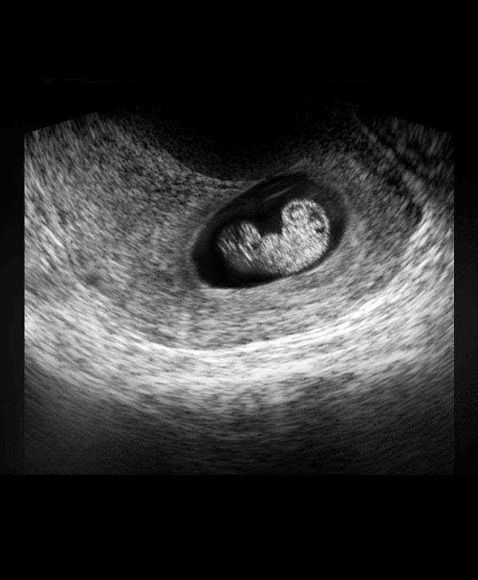

B超图

怀孕进入第7周了,这时的胚胎像一颗豆子,大约有13毫米长。现在如果你能看到自己的身体内部,你会发现胚胎已经有了一个与身体不成比例的大头。而且胚胎的面部器官十分明显,眼睛就像一个明显的黑点,鼻孔大开着,耳朵有些凹陷。

胚胎上伸出的幼芽将长成胳膊和腿,现在看上去已经很明显,手和脚看起来像小短桨一样。其它部分的成长包括垂体和肌肉纤维。现在你听不到胎心音,但是胚胎的心脏已经划分成左心房和右心室,并开始有规律的跳动,每分钟大约跳150下,比你心跳要快两倍。